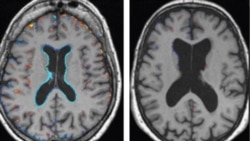

Tsakiyar Kwakwalwar Dan'adam

Taron masana binciken kwakwalwar dan’adam a garin “Silicon Valley” dake jihar California, ta kasar Amurka, sun gabatar da wani bincike, da ya bayyanar da cewar, mafi akasarin mutane a fadin duniya, kanyi amfani da kashi goma sha biyu 12% ne kawai na kwakwalwar su.

Duk mutumin da ya sha maganin, maganin zai taimaka ma kwakwalwar shi, wajen bude sauran kashi tamani da takwas 88% wanda zai cike dari bisa dari 100%. A cewar Dr. Raqif, wannan maganin da suka kirkira mai suna “EnhanceMindIQ” yana tada jijiyoyin dake kwakwalwar mutun don basu damar da ya kamata suyi aikin su yadda ya kamata.